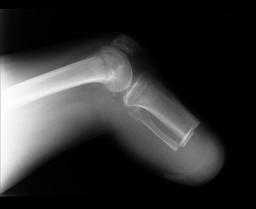

Pre-corrective surgery X-Rays of the damaged right & left legs / ankles

These x-rays were taken at Dr Armendariz’s office, just prior to performing any corrective surgery. As can be seen in these images,

there was no tibia bracing provided by Dr. Keller. Liam was released from Dr Keller’s care with instructions that full weight bearing could

be accomplished within 2 months of Keller’s last surgical procedure. The best example to examine is the second image (from the left) of the

top how. Notice how the bones that should be aligned with the tibia are in fact on the other side of the leg. The third image shows how badly

Liam’s left foot was twisted as a result of the pool placement of the external fixation. What is not obvious is that the screw at the bottom

of the plate on the right fibula missed being screwed into the plate.